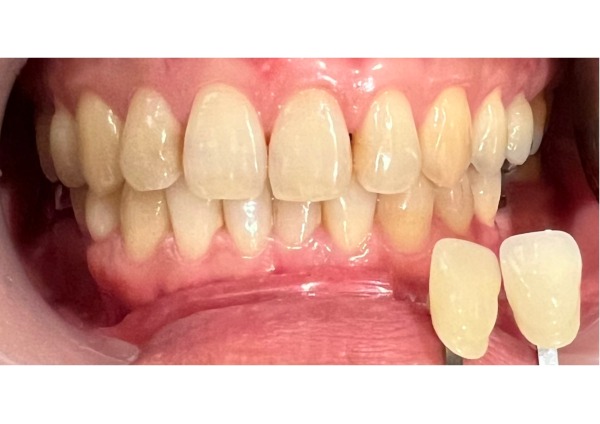

12日目 3ヶ月後にインプラントの被せ物の型を取り、色を合わせる写真を撮影しました。